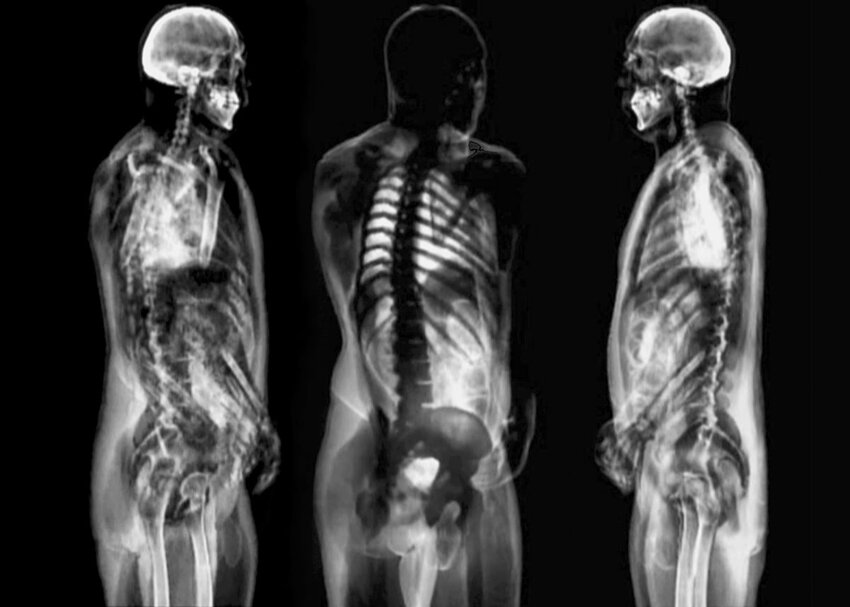

Digital print - Limited edition (10)

50 x 70 cm - 2014 - 2 modules

Price/Prezzo: 800 €

Questa serie procede dall’idea che disseppellire un'immagine dal flusso temporale di un filmato, modificarla per renderla corrispondente alla "impressione" e renderla definitivamente statica tramite la stampa o la pittura sia il suo scopo. Una sorta di impressionismo digitale che invece di andare a pescare le immagini en plein air, le prende da uno schermo dove sono altrettanto fuggevoli, ma con minori rischi di bronchite.